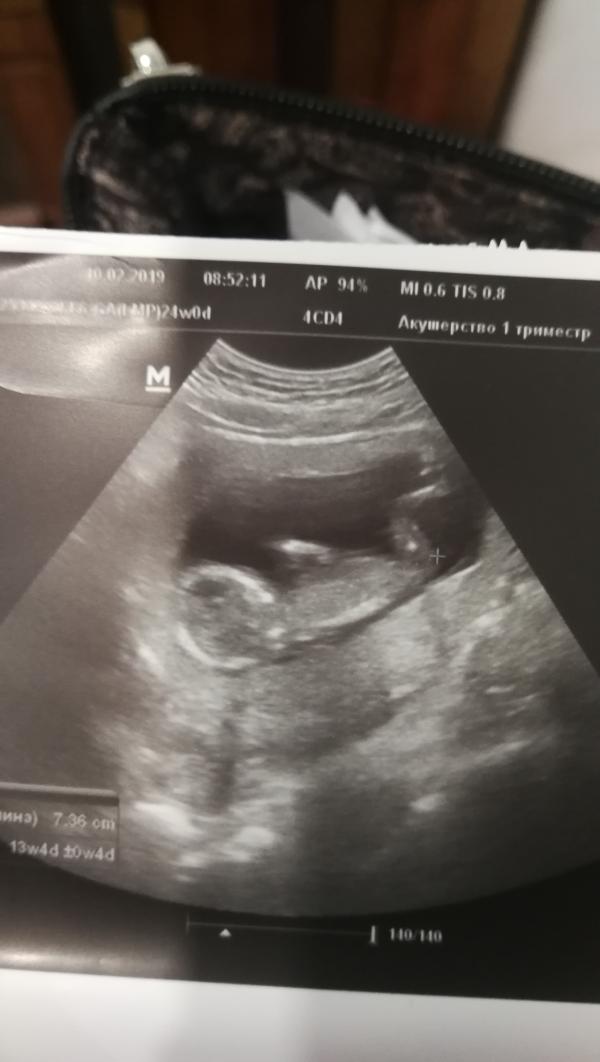

Так надеялась, что в 13 недель скажут кто у нас будет. Со всеми детками мне в 12 недель сказали. А здесь надо набраться терпения. Хотя разницы нет, главное, чтобы здоровенький был) но все равно не терпится узнать)